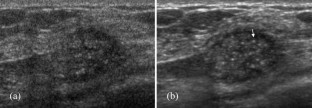

Figure 2